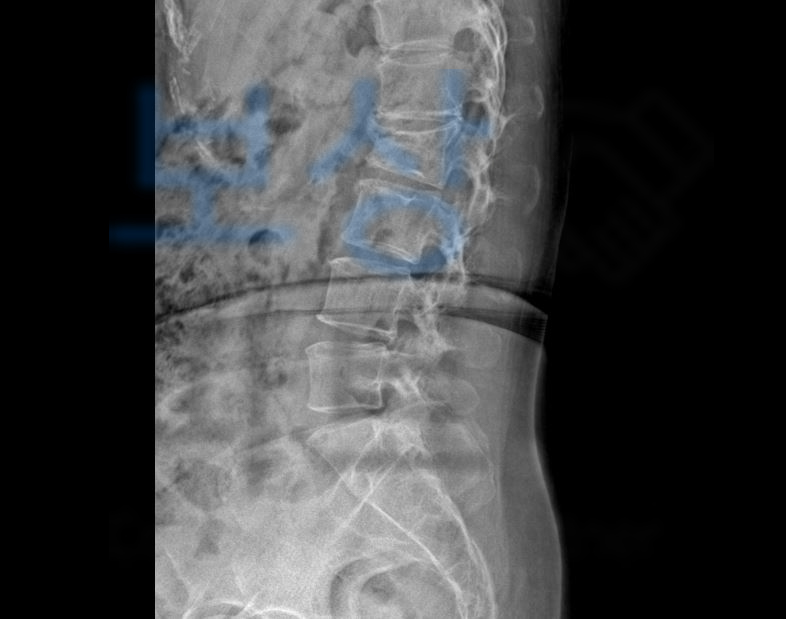

요추2번 척추압박골절 진단을 받아 허리보조기를 착용하시며 12주간의 요양이 필요하였습니다. 내 보험에서 "장해” 담보 가입 유무 확인해주세요. 이@@님은 압박골절 보험보상 을 인터넷에 검색해보시다가 저희 보상파트너로 연락주셨는데요, 저희는의뢰인의 전문가 상담 진행을 위해 영상CD, 보험증권, 의무기록등을 요청드렸고 서류를 검토 후 진행 과정을 설명드렸습니다.

생명보험약관상 척추에 중도의 기형 장해 4급에 해당하셨죠. 저희는 위 진단서를 기초로 손해사정서를 작성하여 보험사에 청구하였고 물론 내부자문과 심사 과정을 거치며 서류 첨부 보완, 보험손해사정사의 이의가 있었지만 보상파트너의 적절한 대응으로 장해율 모두!